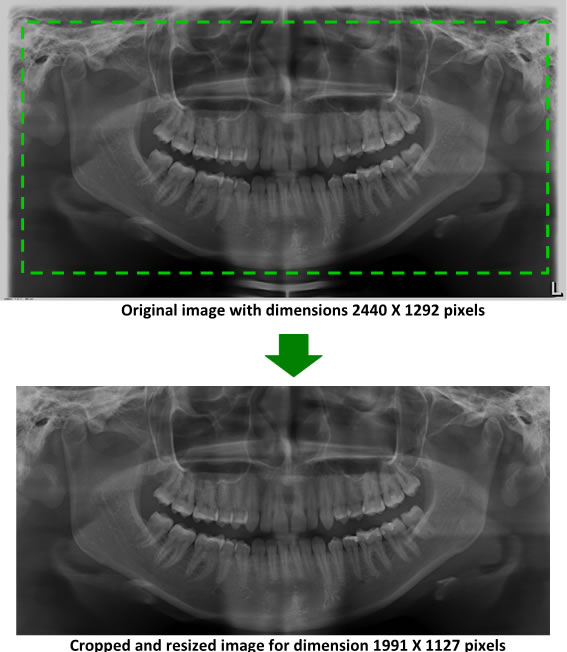

To thoroughly benchmark the methods studied here, the 1,500 images were distributed among 10 categories. The images were named, using whole numbers, in sequential order by category, aiming at not identifying the patients in the study. The process of categorizing the images was performed manually, selecting images individually, counting tooth by tooth, as well as verifying structural characteristics of the teeth. The images were classified according to the variety of structural characteristics of the teeth (see Table 5). Finally, the images were cut out to disregard non-relevant information (white border around the images and part of the spine) generated by the orthopantomograph device. After the clipping process, there was a change in the size of the images to 1991 ×\times 1127 pixels, but without affecting the objects of interest (teeth), as shown in Figure 2. The cropped images were saved on the new dimension to be used in the following stages, which will be presented in the next sections. Figure 3 shows an X-ray image corresponding to each of the categories of our data set.

Refer to caption

Figure 2: Example of the clipping and resizing of the data set images of the present work.